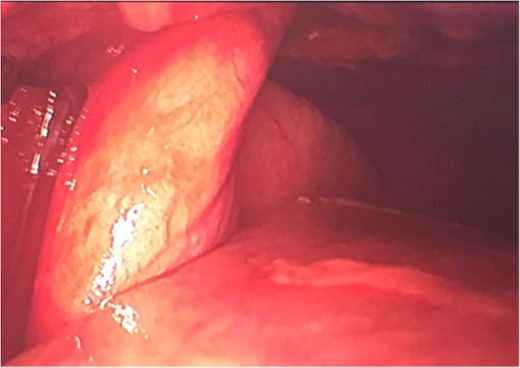

A lingular lung segment protruding through the fifth ICS was observed (Fig. 2), as well as a moderate hemothorax. Lung tissue reduction was performed.